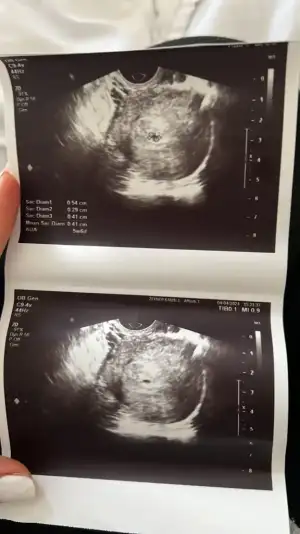

En son gecen cumartesi 3200 cıkmıştı. Bugün 5+3 gittik doktora dayanamayıp. Keseyi, yolk sacı, içinde minnacık da olsa bi bebek beyazlıgını gördük cok şükür. Bir sıkıntı yok gibi duruyor ama 7 cmlik bir kistim cıktı en son asılama öncesi muayenede birsey yoktu ciddi bir şey değil takip edicez kendi kendine kaybolur muhtemelen dedi o biraz aklıma takıldı sadece. Kalp atışı bayram sonrası salı günü gidicez insallah.

Merhabalar benimde sat 12 Şubat 7+5 olduk bizde

Devlet Hastanesi'nde geçen hafta göremedi doktor keseye benzer bişey var dedi korkuttu bende bı 10 gün sonra özele gittim ve kalp atışını dahi duydum gayet sağlıklı gözüküyor dedi doktor inşallah hepimiz sağlıklı bir şekilde kucaklarimiza alırız rabbim hepimize nasip etsin ❤️